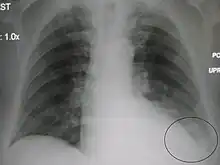

Normal AP CXR

AP CXR showing left lower lobe pneumonia associated with a small left sided pleural effusion

AP CXR showing right lower lobe pneumonia

AP CXR showing pneumonia of the lingula of the left lung

Right upper lobe pneumonia as marked by the circle.

Left upper lobe pneumonia with a small pleural effusion.

Right lower lobe pneumonia as seen on a lateral CXR